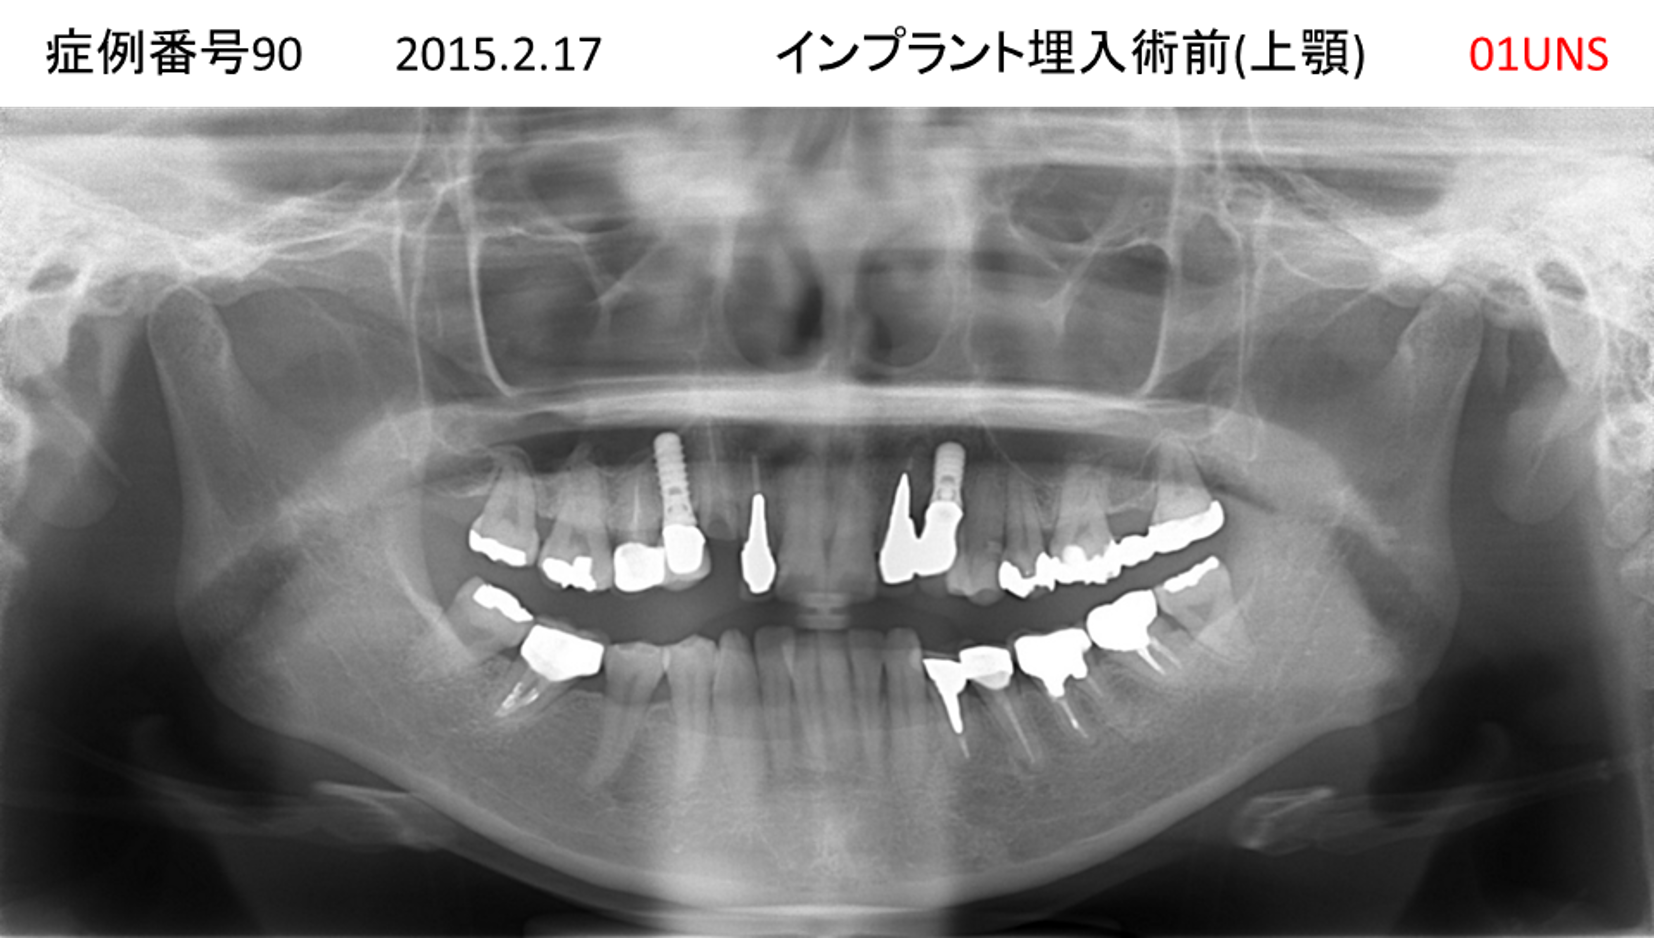

上の前歯が揺れてきた患者様のインプラント症例

| 治療名称 |

インプラント |

| 治療費用 |

390万円+税 |

| 治療期間 |

6か月 |

| 患者さんの症状(主訴) |

上の前歯が揺れてきた。固いものが食べられない。 |

| 治療内容 |

サイナスリフト、抜歯即時インプラント |

| 治療結果 |

上の前歯の揺れが収まった。食べ物がおいしい。 |

| 治療の注意点(リスク/副作用) |

インプラントが壊れたら再治療が必要 |